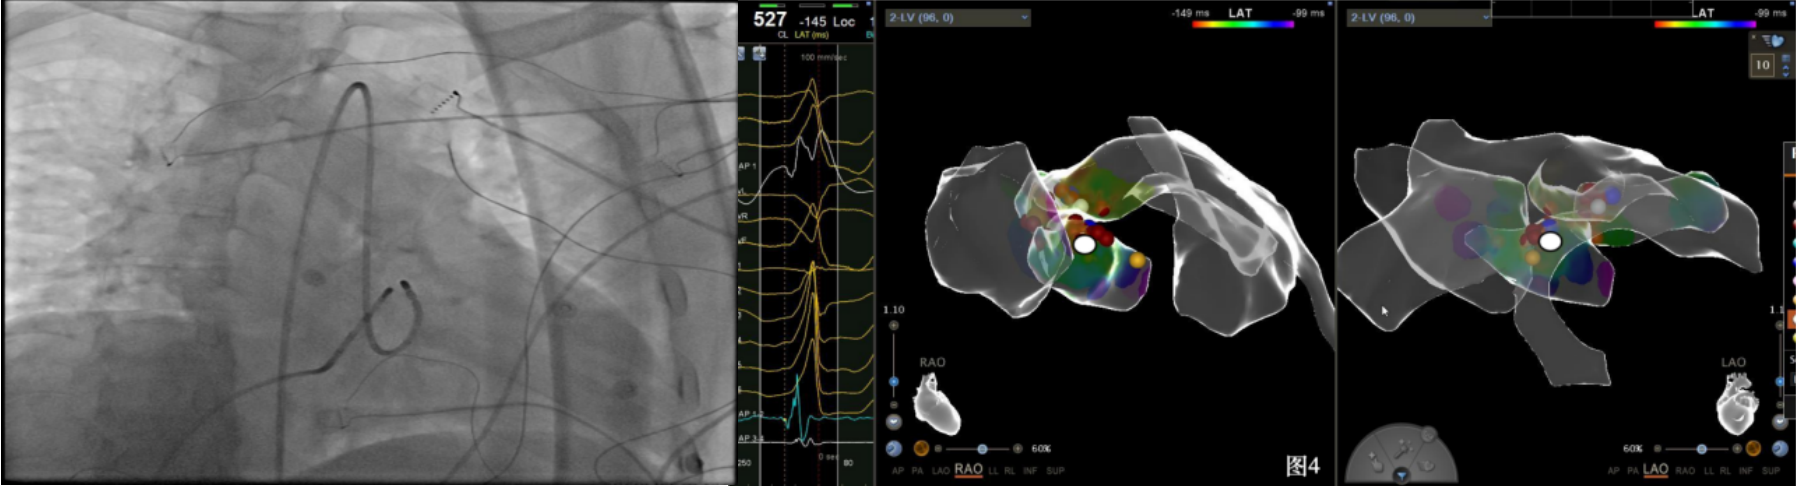

手术中,周明礼团队凭借其丰富的临床经验和精湛的技术,穿刺右股动脉后,将消融大头顺利送入主动脉,于主动脉瓣上标测到最早点(图3红色点)领先体表8ms,电位不理想,果断去到主动脉瓣下左室穹顶部标测,标测到最早点(图4白色点)领先体表25ms,放电消融3s,早搏消失,消融90s后观察2min后,早搏恢复,在该有效点周边补充消融,早搏依旧未能消失,考虑起源点较深,内膜消融未能透壁损伤到起源,随

即穿刺股静脉,将消融大头送至冠状窦内,在GCV远端对应位置标测到最早点(图5绿色点)领先体表27ms,消融后早搏未能消失,周明礼评估起源点偏心外膜,能量依旧不能穿透损伤到起源点,内膜消融基本无效后,果断选择难度系数最为复杂的干性心包穿刺心外膜消融。在导丝的指引下,将消融大头送至心包层(图6),于外膜标测到靶点(图7黄色点)电位领先体表31ms,单极电位无r波且有顿挫,ssummit外膜离冠状动脉较近,比较危险,保证安全,进行了冠脉造影(图7),显示距离LAD和LCx有一定距离,相对安全,随即放电,2s室早消失,10s患者出现心率变慢,该区域走形迷走神经节,消融导致心率减慢,随后保证心率正常的情况下,消融够60s,随后观察半小时,早搏没有恢复,手术成功(图8)。经过不懈的努力,患者恢复了窦率,心脏功能也逐渐恢复正常,手术取得了圆满成功。